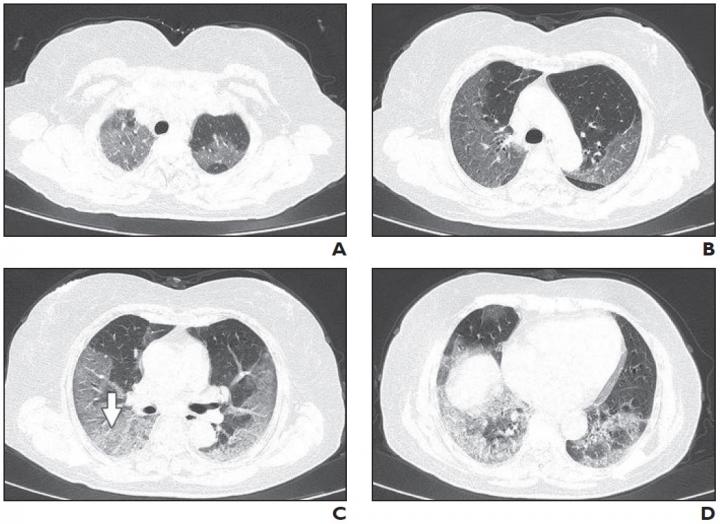

63-Year-Old Woman with Confirmed Coronavirus Disease (COVID-19), Severe Type (IMAGE)

Patient had long-term exposure history to Wuhan and onset symptoms of fever and cough. CT was performed 1 day after admission. A-D, CT images show bilateral diffuse ground-glass opacities and reticulation (arrow, C). CT involvement score is 18.